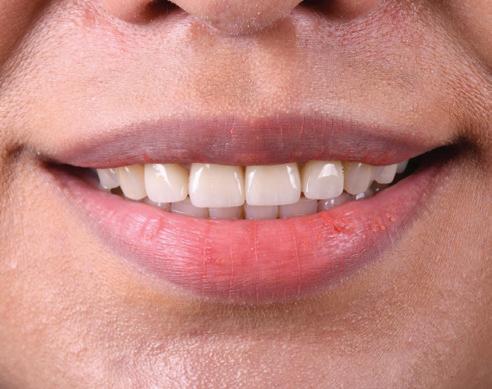

In the clinical case presented here, the patient requested a noninvasive restoration to improve the aesthetics of his anterior teeth. The patient had a diastema between teeth 11 and 21 and showed a dentoalveolar disharmony, characterised by the disproportion between the size of teeth and alveolar ridge. The restorative team proposed an innovative solution consisting of Prettau® Skin® zirconia veneers for the patient. Prettau Skin veneers show a thickness of 0.2 mm and are cemented to the natural teeth with zero to minimal impairment of the tooth substance. Independently of how invasive a restoration can be, it might be difficult for patients to accept and get used to a prosthesis, especially if this is meant to be placed in the anterior region. Therefore, to provide the patient with the best possible care, the workflow included the creation of a mock-up. The present article focuses on the digital workflow for fabricating a tailor-made mock-up and its implementation in the patient’s maxilla.

No doubt, such restorations can significantly help the patient evaluate their new future smile. When used like temporary prostheses, they help the dentist meet the patients’ increasing demands for quick results, providing an aesthetic solution between impression taking and the final restoration. In this case, the mock-up served as an evaluation tool for functional and aesthetic aspects and a temporary restoration between the digital impression phase and the cementation of the final, ultra-thin zirconia veneers.

Once created, the digital mock-up was shown to dentist and patient through a simulation on the 2D pictures to obtain a preview of tooth shapes and proportions. Once the prosthetic solution was approved, the mock-up was milled in Multistratum® Flexible resin to perform the intraoral assessment. Before evaluation in the patient’s mouth, the mock-up was also tested in the physical articulator. To do so, the previously designed models were 3D-printed using the P4000 system, which is already provided with pre-configured settings to facilitate printing.

Mock-up verification: Plaster-free articulation on the model and intraoral test

18. The initial situation and the patient’s smile with the aesthetic mock-up.